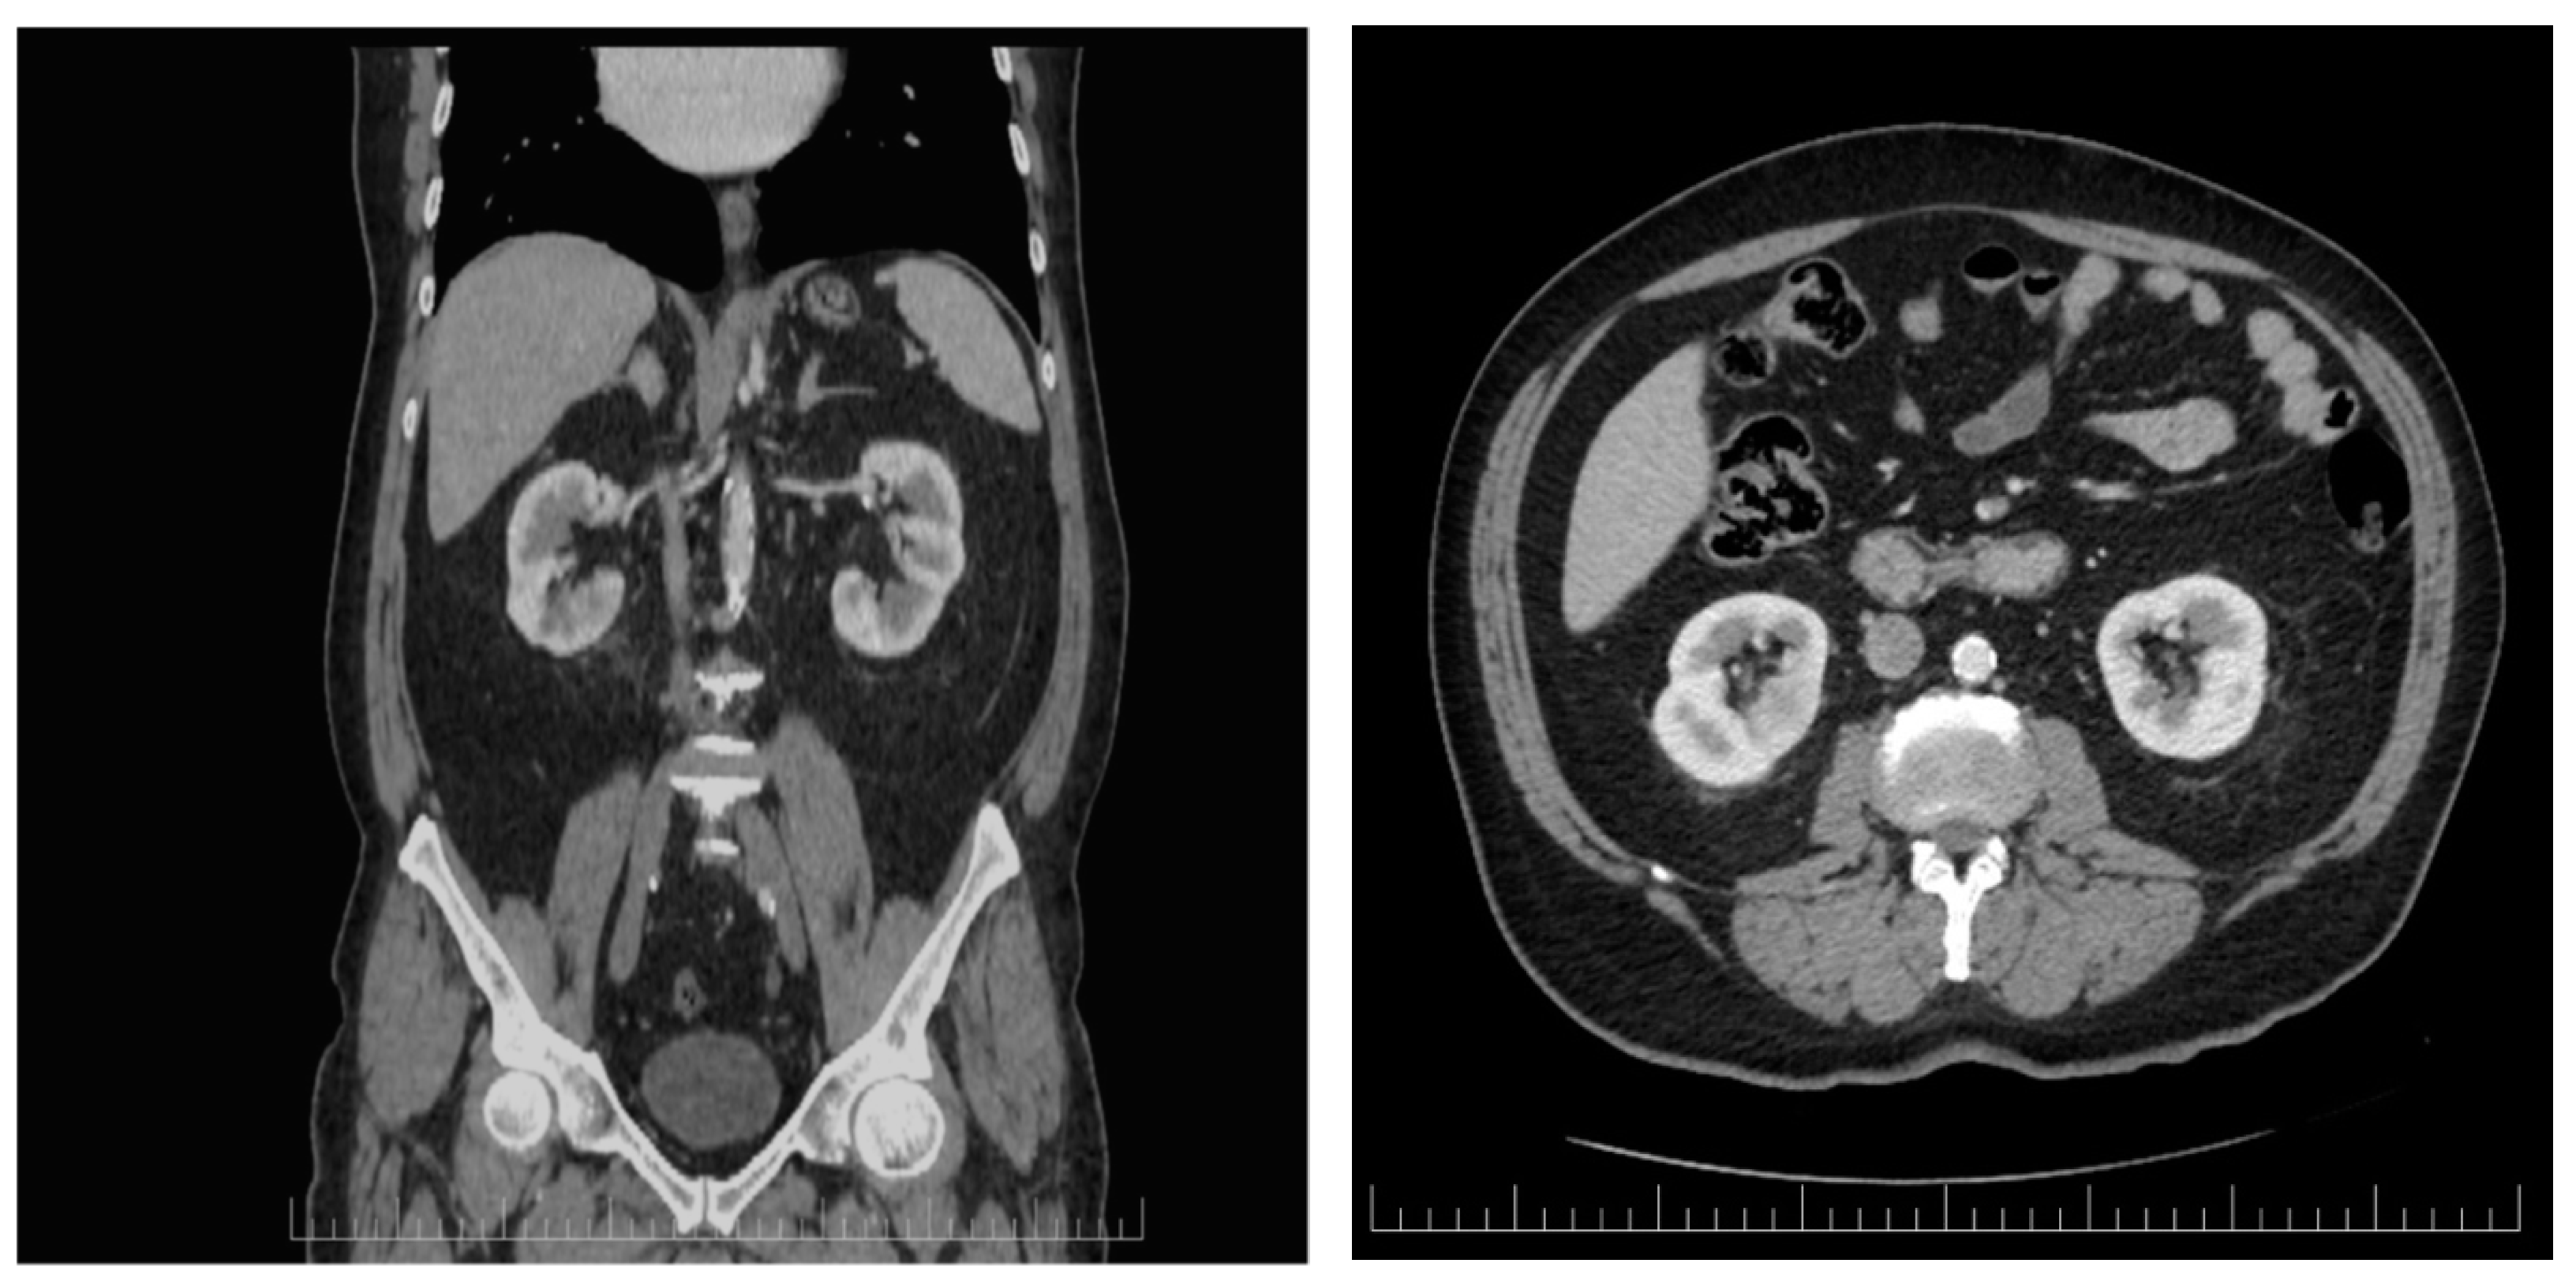

Laboratory evaluation showed leukocytosis, and a high level of C reactive protein at baseline. The detailed results of his blood count and other pertinent labs are shown in Table 2. The Urine blood culture was positive for a UTI with Escherichia coli. The E. coli was sensitive to amikacin, cefoperazone and/or sulbactam, gentamicin, imipenem, meropenem, natamycin, nitrofurantoin, and piperacillin and/or tazobactam. An enhanced CT scan was performed based on abdominal US suspicion of a renal mass. The imagistic evaluation showed fluid mass in the inferior pole of the right kidney with surrounding inflammatory changes concerning renal abscess, measuring 15.3 × 21.8 mm, as shown in Figure 1. A differential diagnosis was made for an infected renal cyst. There were inflammatory changes in the right renal collecting system associated with the thickening of the urothelium and bladder wall without any obstructive pathologies or secondary determining hydronephrosis.

Figure 1.

The first CT scan evaluation revealing lower pole fluid collection measuring 15.3/21.8 mm suggestive for renal abscess.

Active fluid and electrolyte supplementation and symptomatic medications were administered. According to the active guideline recommendations for small renal abscesses (<3 cm), no percutaneous or open drainage were necessary as the initial treatment in this case [14]. The patient’s condition was periodically monitored by blood count assessment and ultrasonographic evaluation during his hospital stay. The follow-up enhanced CT scan performed on the 14th day of hospitalization revealed that the renal collection was in complete remission (Figure 2). He was discharged in stable condition after a few days, and Dapagliflozin was withheld from the patient.

Figure 2.

Axial and coronal enhaced CT scan performed after 2 weeks of continuous antibiotic administration revealing that the renal abscess completely dissapeared.